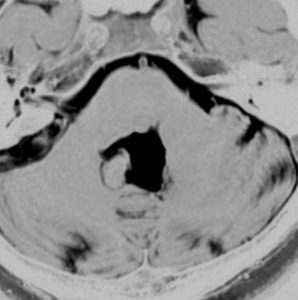

小脳橋角部の典型的な類表皮のう胞 epidermoid cyst

20代の女性が右の激しい顔面痛(三叉神経痛)で発症しました。左から順にMRIのT1強調画像,T2強調画像,拡散強調画像です。髄液と同じように見えますので脳の形の変形だけで腫瘍があることを疑います。でも,拡散強調画像では真っ白になるので腫瘍が存在していることがわかります。三叉神経は腫瘍の真ん中にあって伸びています。

術後の写真です。普通のMRIでは全部取れているかどうかわかりませんが,左の拡散強調画像をみるとおよそ全部取れていることがわかります。でも完全摘出の完全な証明は画像ではできません。術後10年くらい経ちますが再発はありませんでした。